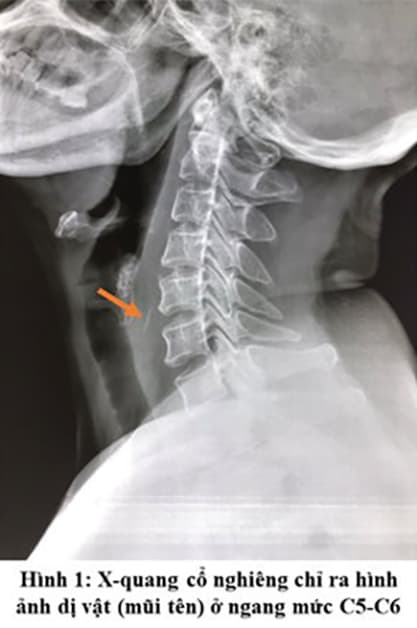

Hình ảnh chụp X-quang xác định dị vật họng miệng